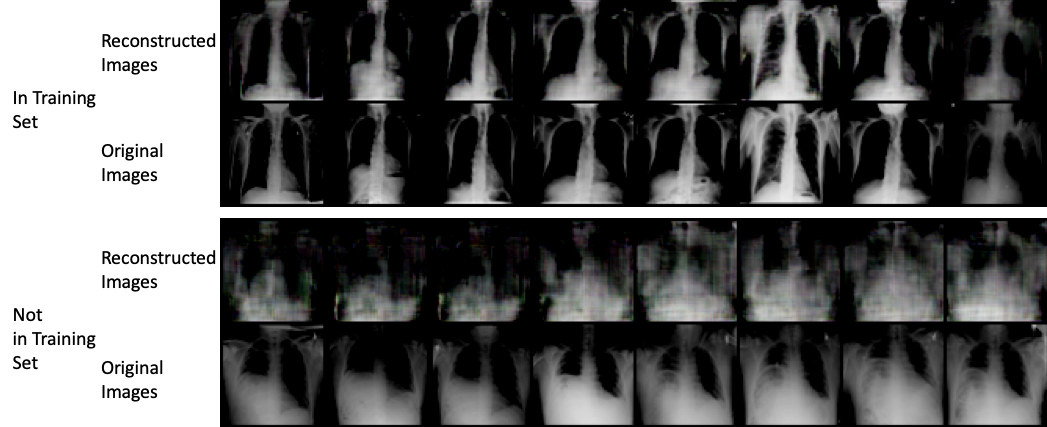

We also qualitatively visualize the generated results on ChestX-ray8 data in Figure 2. The first two rows show the generated and original images when the original (target) ones are actually contained in the training data. It is clear that the generated instances visually look similar with the original ones which indicates high attack/inference success rate. On the contrary, the lower two rows show similar instances while the original images are not in the training data. The results show that this time the generated instances are more random and far from the original ones.